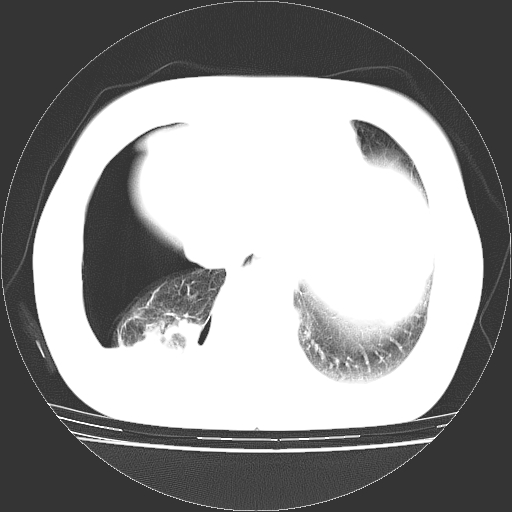

以下是引用zhangzhongshou在2008-3-22 12:52:00的发言:[br]1、右侧液气胸。[br]2、腹水。建议进一步检查。

以下是引用鲁巨ct在2008-3-22 14:10:00的发言:[br]1、右侧液气胸,右中下叶节段性不张。[br]2、腹水,建议上腹部ct检查

以下是引用zjzjr在2008-3-22 17:19:00的发言:[br]1、右侧液气胸,右下叶节段性不张。[br]2、腹水,建议上腹部ct检查